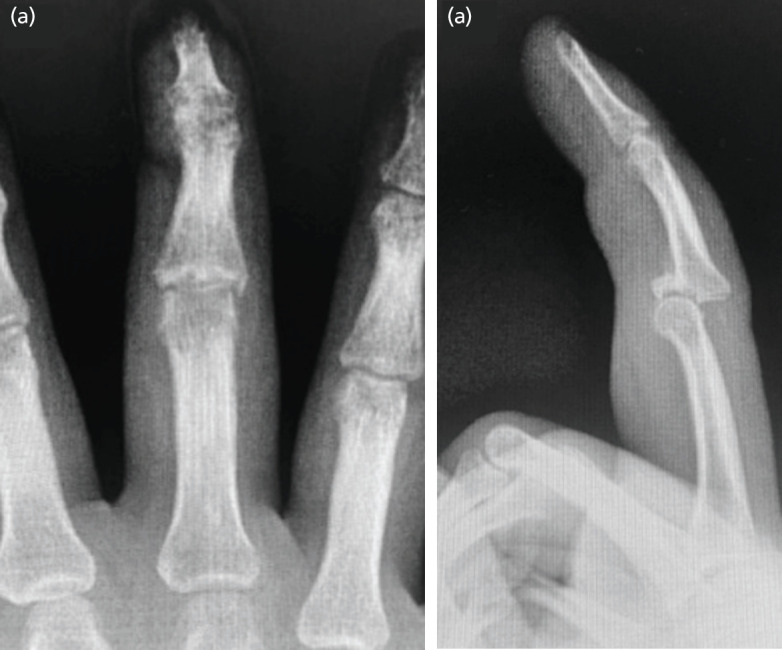

Wide-awake local anaesthesia, no tourniquet (WALANT) has been reported for upper extremity procedures of varying complexities ranging from simple tendon repairs to more complicated soft tissue and bony reconstructions. Hemi-hamate arthroplasty under WALANT has yet to be described in English literature. We report a case of a chronic dorsal PIPJ fracture-dislocation who underwent open reduction followed by Hemi-hamate Arthroplasty under wide-awake anaesthesia. There was adequate visualization during the surgery with no additional anaesthesia required. Active intra-operative range of motion and joint stability testing was possible with no pain experienced throughout the procedure. 10-month post-operative follow-up showed excellent range of motion with occasional tolerable pain during maximal finger flexion and power grip. Wide-awake anaesthesia is a viable and safe alternative for hemi-hamate arthroplasty.